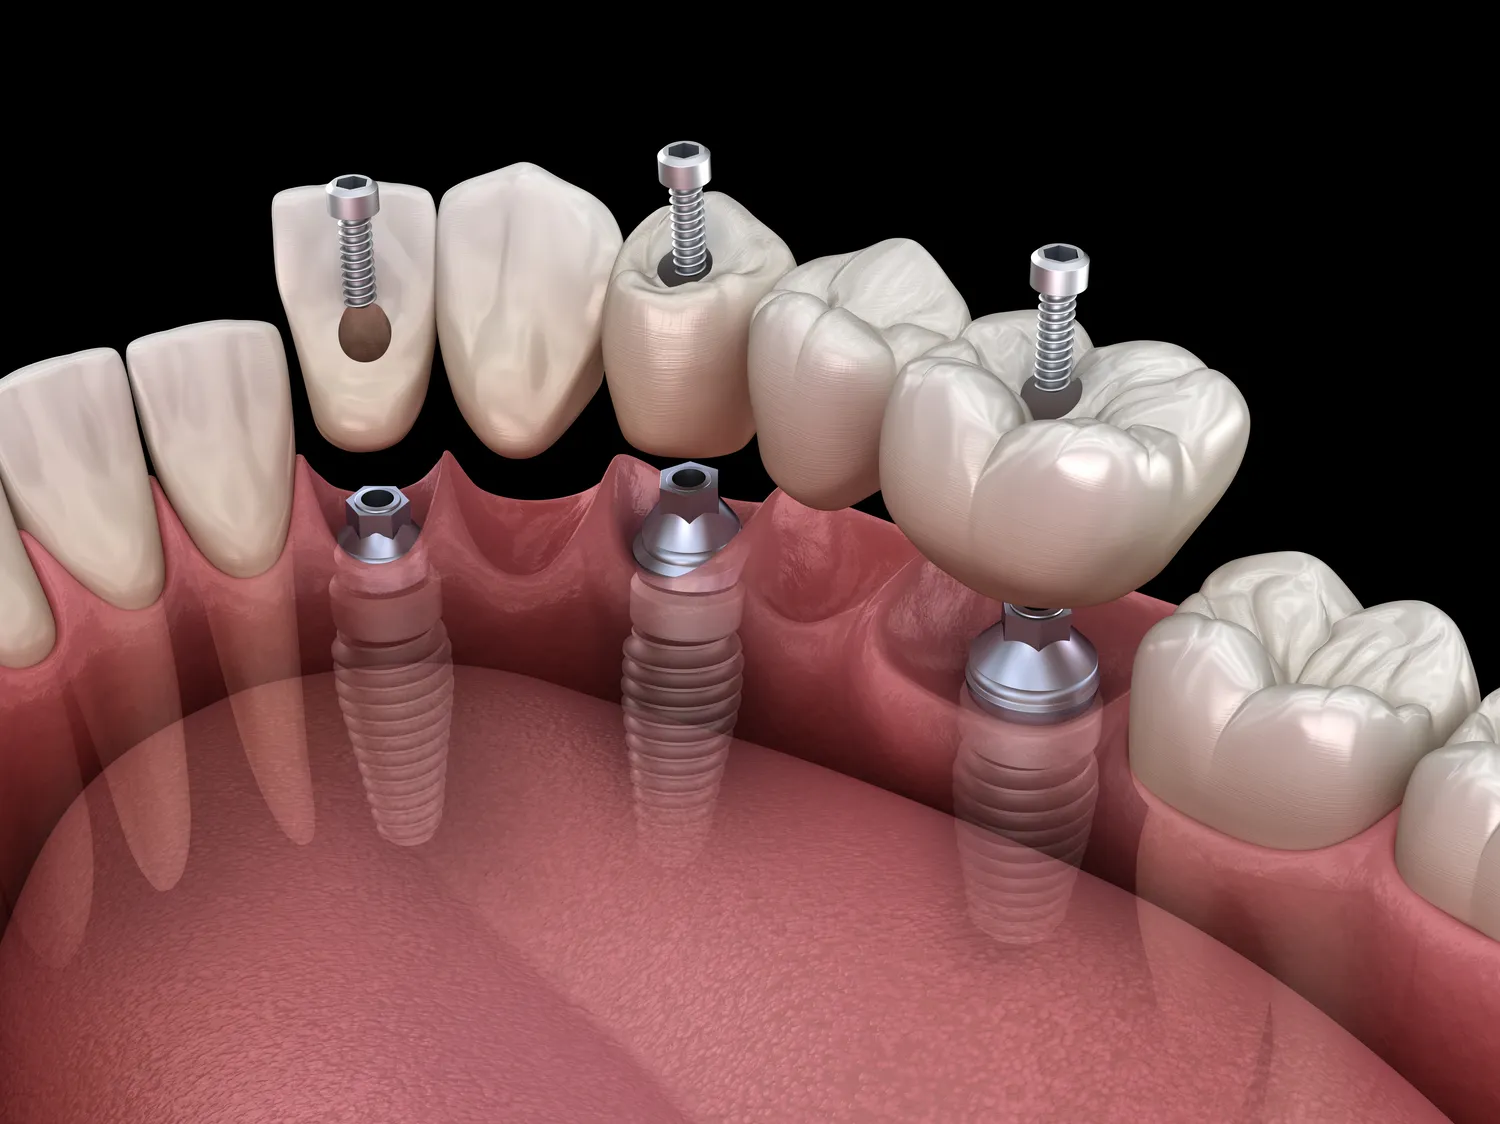

Proces leczenia implantologicznego w Warszawie składa się z kilku kluczowych etapów, które mają na celu zapewnienie bezpieczeństwa oraz skuteczności zabiegu. Pierwszym krokiem jest konsultacja stomatologiczna, podczas której lekarz ocenia stan zdrowia pacjenta oraz wykonuje niezbędne badania diagnostyczne. Na podstawie wyników badań lekarz podejmuje decyzję o możliwości wszczepienia implantu oraz dobiera odpowiedni typ implantu do indywidualnych potrzeb pacjenta. Kolejnym etapem jest zabieg chirurgiczny, który polega na wszczepieniu implantu w kość szczęki lub żuchwy. Po tym etapie następuje okres gojenia, który może trwać od kilku tygodni do kilku miesięcy, w zależności od indywidualnych warunków anatomicznych pacjenta. Po zakończeniu procesu gojenia następuje etap protetyczny, podczas którego na implancie mocowana jest korona protetyczna, co przywraca pełną funkcjonalność i estetykę uzębienia.

Wiele osób, które rozważają wszczepienie implantów zębowych, ma liczne pytania dotyczące tego procesu. Jednym z najczęściej zadawanych pytań jest to, jak długo trwa cały proces leczenia. Zazwyczaj od momentu pierwszej konsultacji do zakończenia leczenia może minąć kilka miesięcy, ponieważ wymaga to czasu na gojenie się kości po wszczepieniu implantu oraz na wykonanie korony protetycznej. Innym istotnym pytaniem jest kwestia bólu związanego z zabiegiem. Warto wiedzieć, że podczas wszczepienia implantu stosuje się znieczulenie miejscowe, co sprawia, że pacjenci zazwyczaj nie odczuwają bólu w trakcie zabiegu. Po jego zakończeniu mogą wystąpić pewne dolegliwości, które można złagodzić za pomocą leków przeciwbólowych. Pacjenci często pytają również o trwałość implantów – przy odpowiedniej higienie i regularnych wizytach kontrolnych mogą one służyć przez wiele lat, a nawet przez całe życie.

Rehabilitacja po wszczepieniu implantu to kluczowy etap procesu leczenia, który ma na celu zapewnienie prawidłowego gojenia się tkanek oraz integracji implantu z kością szczęki lub żuchwy. Po zabiegu pacjenci powinni ściśle przestrzegać zaleceń lekarza dotyczących diety oraz aktywności fizycznej – przez pierwsze dni zaleca się spożywanie miękkich pokarmów i unikanie intensywnego wysiłku fizycznego. Ważne jest także monitorowanie stanu miejsca wszczepienia implantu – jeśli pojawią się jakiekolwiek niepokojące objawy, takie jak silny ból czy obrzęk, należy niezwłocznie skontaktować się ze specjalistą. Regularne wizyty kontrolne są niezbędne do oceny postępów gojenia oraz wykrywania ewentualnych komplikacji na wczesnym etapie. W miarę upływu czasu lekarz będzie mógł ocenić stabilność implantu i zdecydować o dalszym postępowaniu – zazwyczaj po kilku miesiącach następuje etap protetyczny polegający na mocowaniu korony protetycznej na implancie.